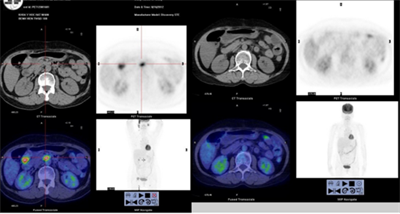

Case lâm sàng: Ứng dụng trí tuệ nhân tạo (Artificial intelligence – AI) trong chẩn đoán và điều trị sớm Ung thư phổi tại Trung tâm Y học hạt nhân và Ung bướu, Bệnh viện Bạch Mai

Theo GLOBOCAN 2022, ung thư phổi đứng đầu về số ca mới mắc (2.480.301 ca mới mắc chiểm 12.4%) và dẫn đầu số ca tử vong (1.817.172 ca tử vong chiếm 18.7%) trên toàn thế giới.  Tại Việt Nam tỷ lệ mắc ung thư phổi xếp thứ ba 13,5% lệ tử vong...